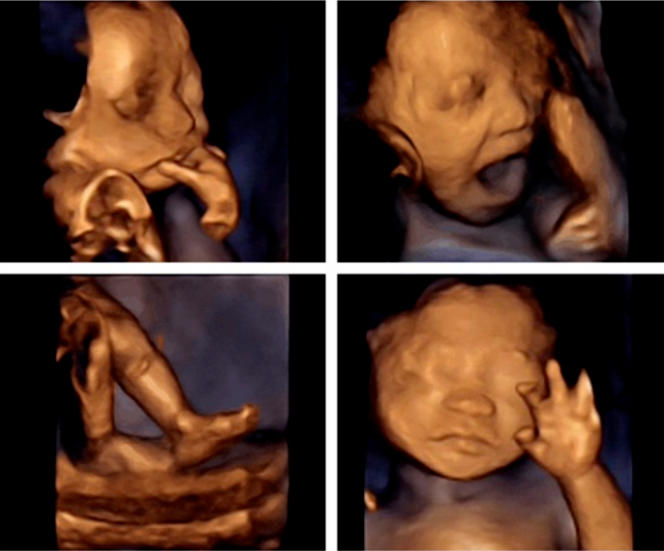

四维彩超是孕中期非常重要的一个检查

它可以检查宝宝的各器官及发育是否正常

排查胎宝宝是否存在结构缺陷

排除重大心脏畸形

还能检查胎宝宝的胎盘情况以及羊水情况